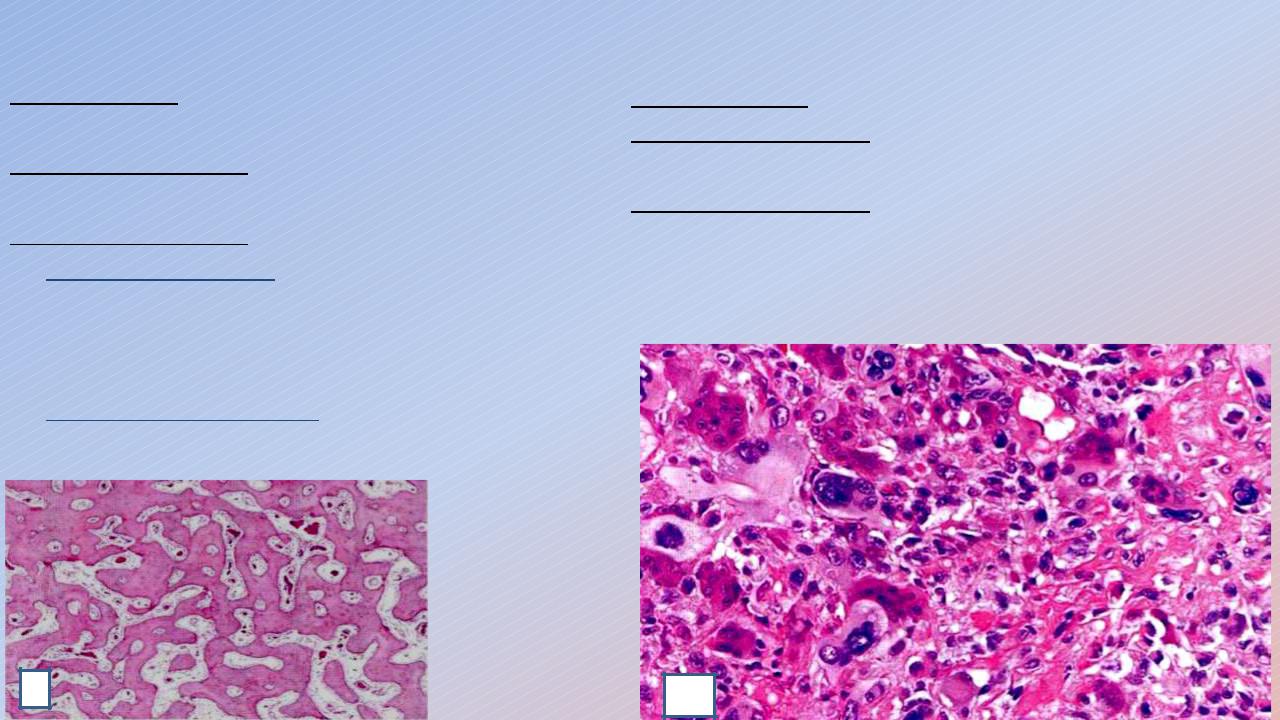

1. Остеома:

Локализация: губчатые и трубчатые кости, язык.

Макроскопически: узловое образование очень плотной консистенции, серо-белого цвета.

Микроскопически:

Губчатая остеома – состоит из беспорядочно расположенных костных балочек, между которыми волокнистая соединительная ткань (1).

Компактная остеома – плотно скомпонованная костная ткань.

2. Остеосаркома:

Локализация: та же, что и у остеомы. Макроскопически: образование без четких границ плотной консистенции серо-белого цвета. Микроскопически: состоит из беспорядочно расположенных недифференцированных остеобластных клеток (2).